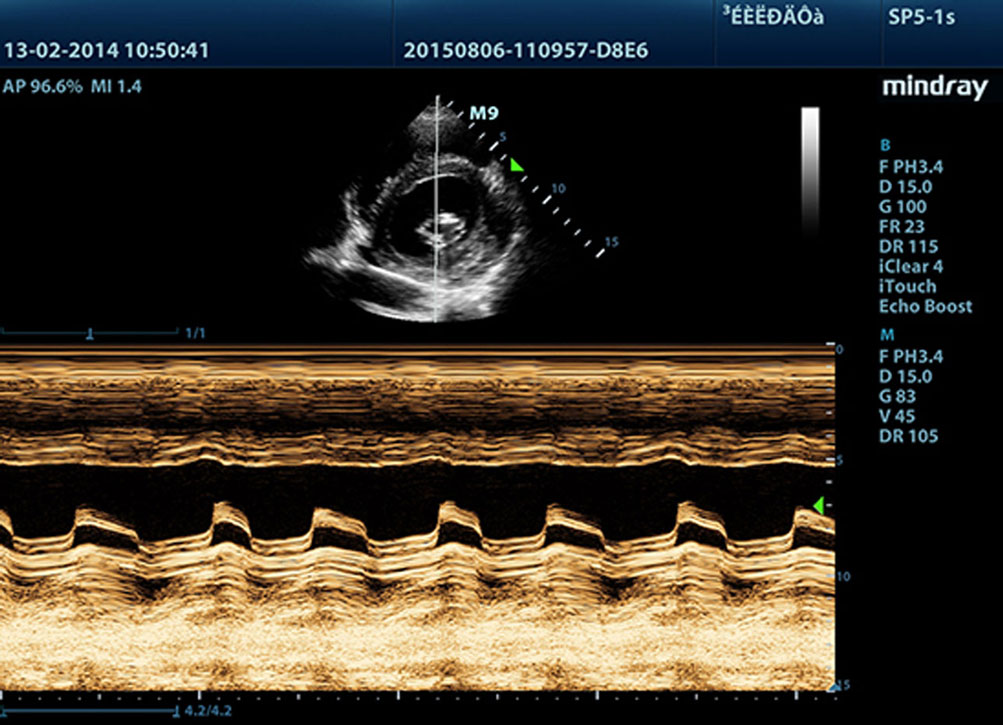

Free Xros M?

Enfatizzazione di una linea anatomica precisa tramite posizionamento libero di linee di campionamento in qualsiasi angolazione. Ottenimento di immagini migliori attraverso la visualizzazione simultanea di un massimo di 3 linee di campionamento.

Free Xros CM?

Valutazione con precisione del movimento del miocardio in diverse fasi, e determinazione simultanea della sincronizzazione del miocardio. Alto frame-rate che fornisce risultati accurati